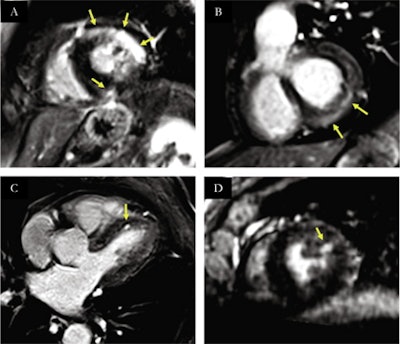

Overall, a definite diagnosis using the new sequence was obtained in 15 out of 20 of the COVID-19 patients, including myocarditis in nine, multiple microinfarctions in two, myocardial infarction in two, and takotsubo cardiomyopathy in two.

In patients with structural heart disease, all LGE-positive segments on LR-LGE were also detected on HR-LGE (80/391) with 21 additional enhanced segments visible only on HR-LGE (101/391).

In all patients (n = 43), including those in the validation study, the technique allowed for acquisition times of 7 minutes and 21 seconds at 1.25 mm3 resolution, compared with an average of approximately 16 minutes at 1.4 mm3 isotropic resolution on low-resolution late gadolinium enhancement (LR-LGE), the researchers found. Compared with LR-LGE, HR-LGE also showed higher image quality and comparable signal intensity differences.